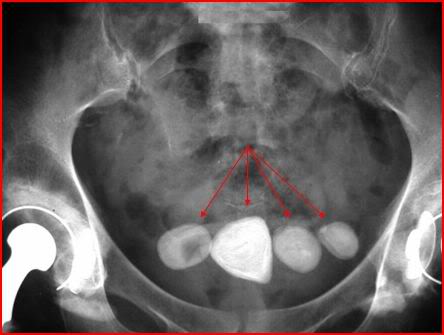

Nhiều người do công việc, thói quen thường hay nhịn tiểu, việc làm này có hại cho sức khỏe, bởi nước tiểu có đến hàng trăm loại chất thải khác nhau của cơ thể. Khi bị ứ trong bàng quang có thể dẫn đến sỏi tiết niệu, sỏi bàng quang khi di chuyển gây tổn thương các bộ phận này tạo môi trường cho vi khuẩn dễ xâm nhập vào cơ thể và gây nhiễm trùng tiểu, viêm bàng quang. Nhịn tiểu cũng sẽ làm cơ thể mất phản xạ tiểu theo đúng chu kỳ, dẫn tới tiểu són, tiểu rắt và lâu ngày, sẽ gây ra viêm niệu đạo, viêm bể thận, và ảnh hưởng đến chức năng thận. Bàng quang con người cũng như một cái túi, trung bình chứa được 250 - 300ml nước, Khi dung tích bàng quang khoảng 350ml thì bắt đầu có dấu hiệu căng giãn gây cảm giác mót tiểu, nếu thường xuyên bị căng và nhịn tiểu lâu có thể gây vỡ bàng quang.